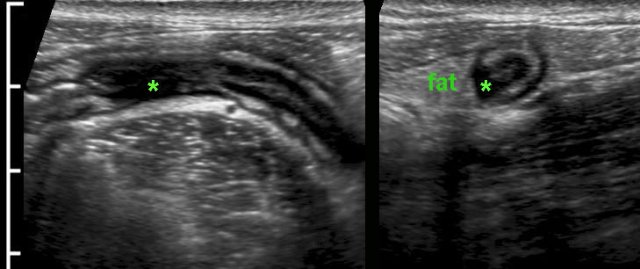

In patients with manifest active Crohn’s disease, the normal US architecture of the bowel wall may be lost diffusely.

Note the hyperechoic fatty tissue (fat) around the ileum, representing the inflamed mesentery and omentum, trying to wall off the imminent perforation.

In cases like this, the altered morphology and luminal narrowing may mimic malignancy.

Sometimes, the US image can be quite confusing.

In this patient, the irregular, asymmetrical wall thickening of the cecum with adjacent inflamed fat (*) and  encroachment of the appendix (arrow) suggested malignancy with desmoplastic reaction and ingrowth in the base of the appendix.

Concomitant wall thickening of the terminal ileum and especially the transmural changes (arrowhead) in the distal appendix, suggested the correct diagnosis of ileocecal Crohn’s disease with involvement of the appendix.